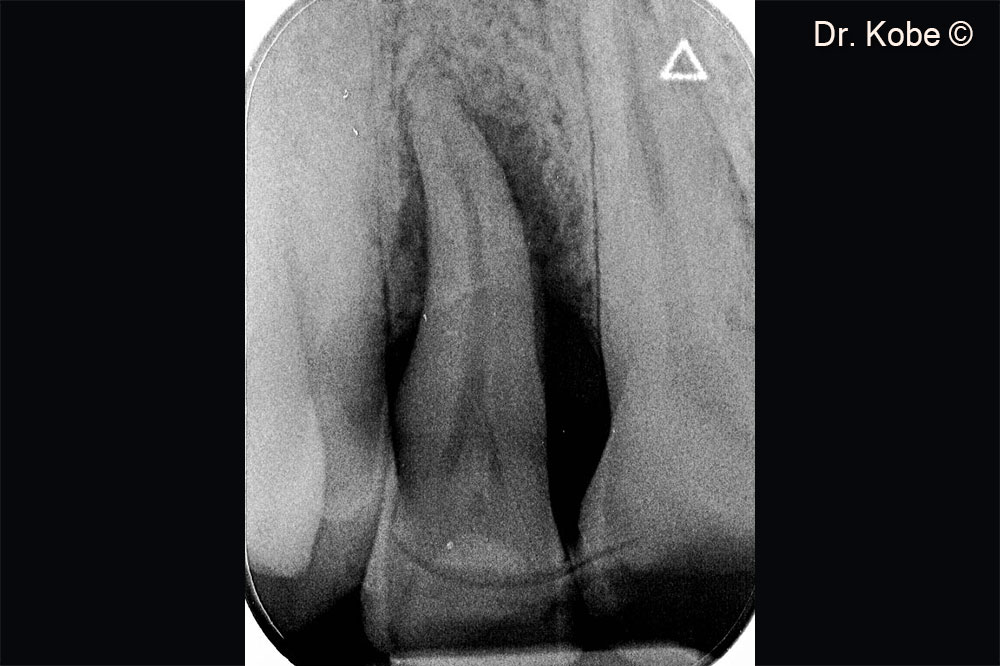

Khuyết tật xương theo chiều dọc trên phim chụp X-Quang